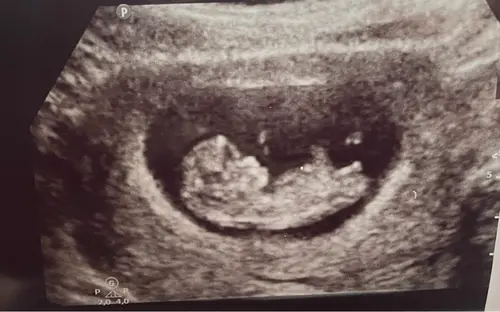

Iemand die een gokje durft te wagen? Deze echo is van precies 11 weken zwangerschap. De vk heeft er een duidelijke foto van de nub bij gedaan, zodat we zelf konden puzzelen haha. Ben benieuwd wat jullie denken! 🩵🩷

Iemand enig idee? De vk zei dat ze (maar totaal nog niet betrouwbaar) dacht dat het weer een jongetje zou worden😊 Ben nu precies 11 weken.

Nub is dat witte streepje helemaal rechts. Ik vind de foto net niet duidelijk. De stand is namelijk meisje (maar zo staan ze tot 12 weken dus allemaal) maar het uiteinde lijkt wel iets weg te hebben van een jochie.